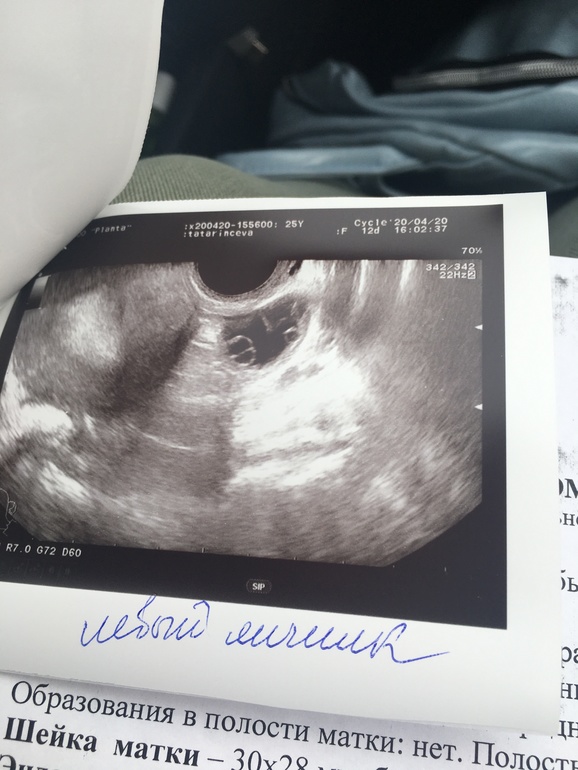

Ну я так понимаю,у Вас в левом яичнике киста(предположительно фолликулярная). У меня часто такая картина была. А вот эндометрий очень даже пышный для 12ДЦ

Если она фолликулярная,то это абсолютно не страшно))))Я более 10 лет с ними сталкивалась

Я вижу в ЛЯ ЖТ, а в ПЯ ещё не лопнувший ДФ